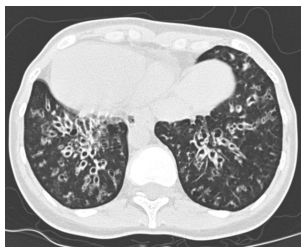

12.病人胸腔電腦斷層如圖示,病人主要是何種疾病? (A)慢性阻塞性肺病 (B)支氣管擴張症 (C)肺炎 (D)肺膿瘍